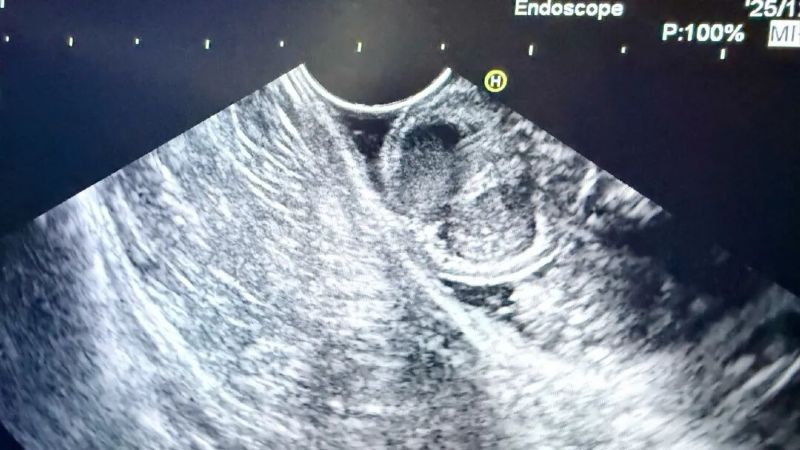

為進一步明確病變性質與起源層次,消化內科二病區張榮主任團隊為患者安排了增強CT、超聲內鏡等一系列精密檢查。完善上述檢查后,結合影像學特征考慮良性病變可能性大,但仍無法完全排除惡性可能,病變性質的最終判定,必須依靠完整切除標本后的病理診斷。

患者超聲內鏡以及胃鏡圖